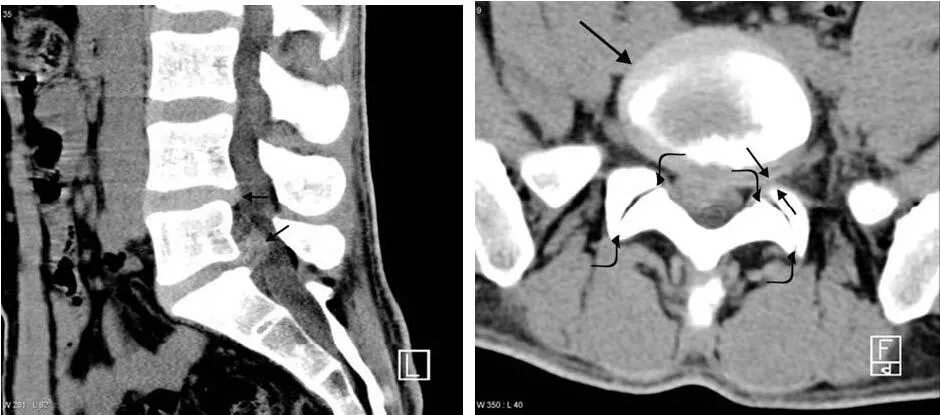

Как делают кт пояснично крестцового отдела